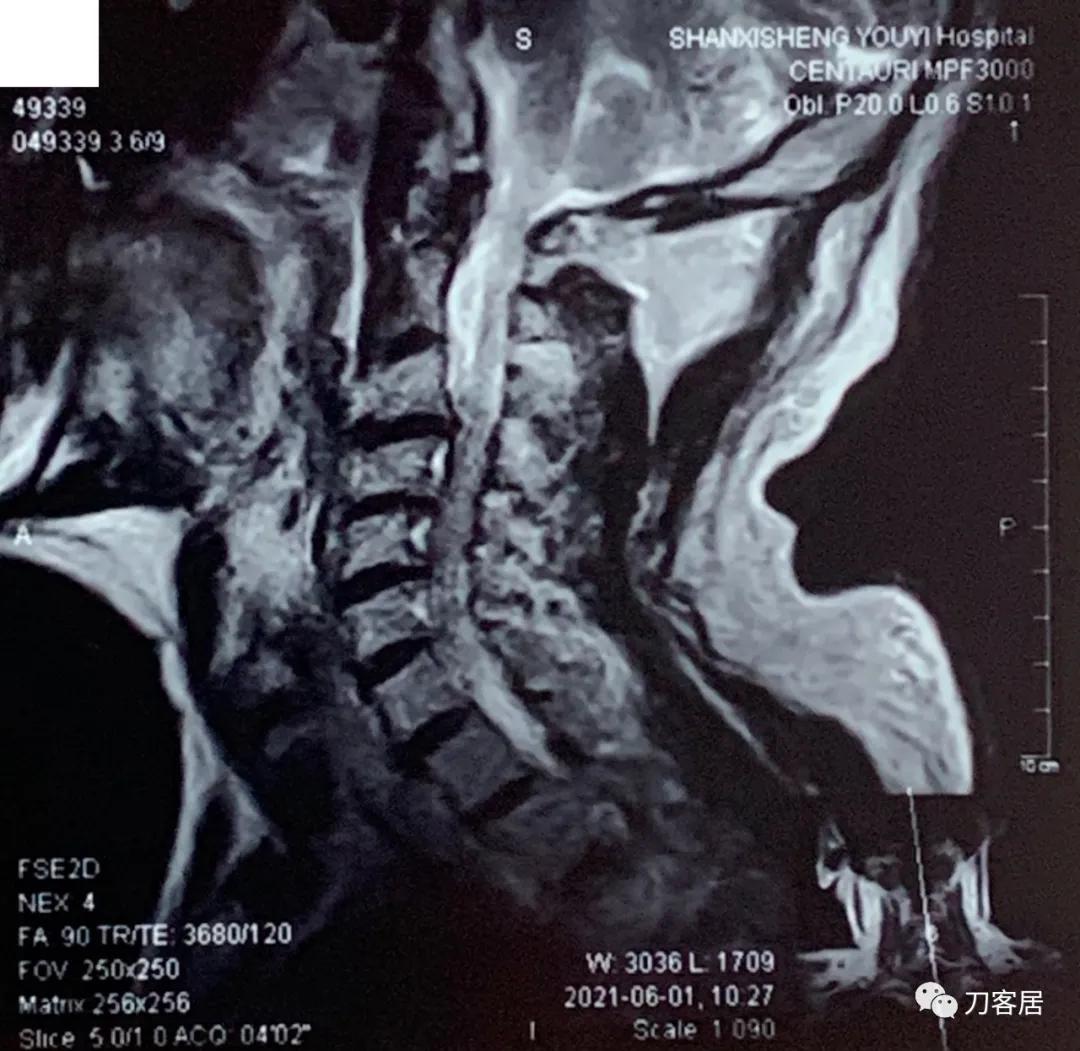

自带颈椎MRI提示颈3-4,颈4-5,颈5-6,颈6-7椎间盘突出,椎管狭窄。目前无明确上位神经损伤表现,暂不处理。骨密度提示骨量减少,但因患者的临床表现,符合骨质疏松症的表现,夜间痛明显,活动后缓解,且已高龄,虽然患者的颈椎MRI片子显示多节段椎间盘突出,椎管狭窄,比较严重, 但无明确的神经损伤表现,病理反射阴性,所以,选择保守治疗,先行抗骨质疏松,以观疗效后决定是否在未来需要手术治疗。

诊断: 骨质疏松症,颈3-7椎间盘突出,颈椎管狭窄。

2021年6月1日外院的颈椎MRI